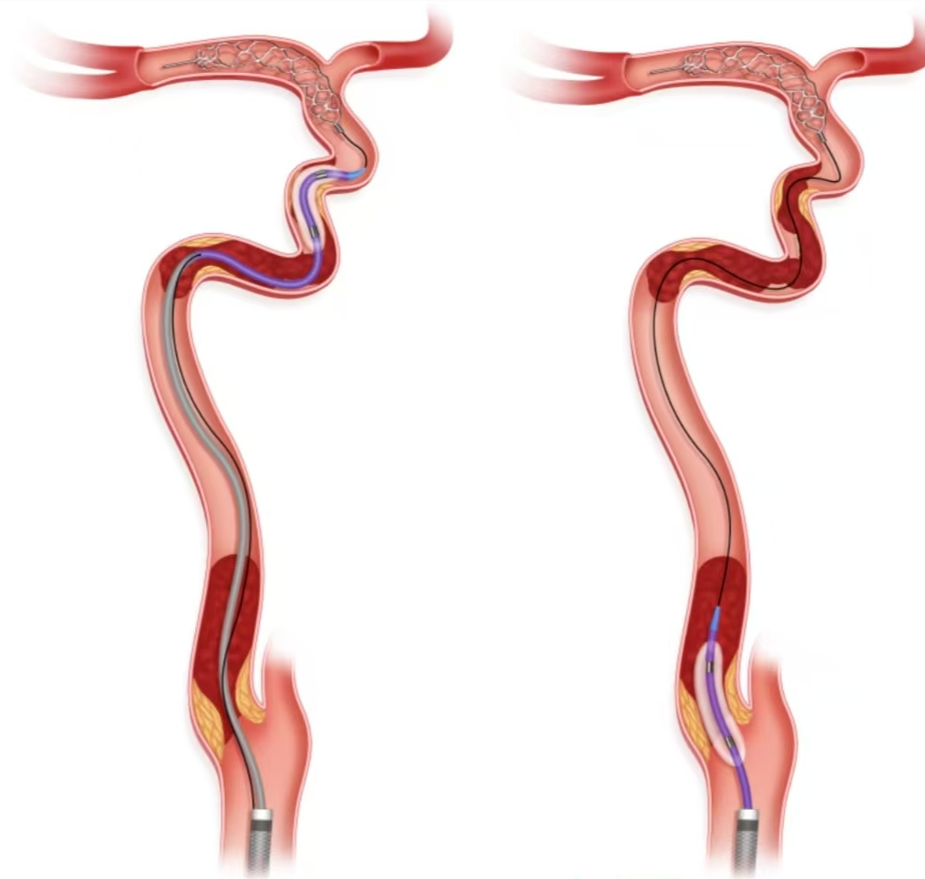

步骤一:释放Syphonet®取栓支架远端保护。

微导丝、微导管突破闭塞段后,将Syphonet®取栓支架跨越M1段与颈内动脉末端释放,起到颅内远端血管的保护作用。

步骤二:造影初步鉴别病变性质。

利用盲交换技术将微导管撤出体外,通过指引导管足量、足压力造影,初步鉴别闭塞段病变性质

步骤三:球囊扩张导管扩张后足量、足压力造影判断闭塞性质。

沿Syphonet®取栓支架输送导丝送入小直径的球囊扩张导管(2mm-2.5mm),由远及近依次对可疑病变部位进行扩张,后再次足量、足压力造影,明确闭塞段内原始病变部位、继发血栓部位和假性闭塞部位。

步骤四:球囊/支架血管成形。

选取合适的球囊扩张导管扩张残余的严重狭窄部位。在出现明显限流性夹层、斑块回缩明显限制前向血流的部位,可考虑经Syphonet®取栓支架输送导丝送入支架系统,支架释放后进行球囊后扩张以提高支架贴壁性,降低再狭窄和再闭塞率。

步骤五:造影确认后结束手术。

造影确认Syphonet®取栓支架内无血栓、前向血流稳定后,用球囊扩张导管或微导管回收Syphonet®取栓支架,系统整体撤出体外,结束手术。

补充步骤:在球囊扩张过程中如发现栓子负荷大,可将血栓抽吸导管反复抽吸清理血栓。

持续负压下前进血栓抽吸导管,反复抽吸,清理闭塞管腔内的血栓。如果造影发现Syphonet®取栓支架内捕获了脱落的血栓,则回撤Syphonet®取栓支架,清理支架内血栓。